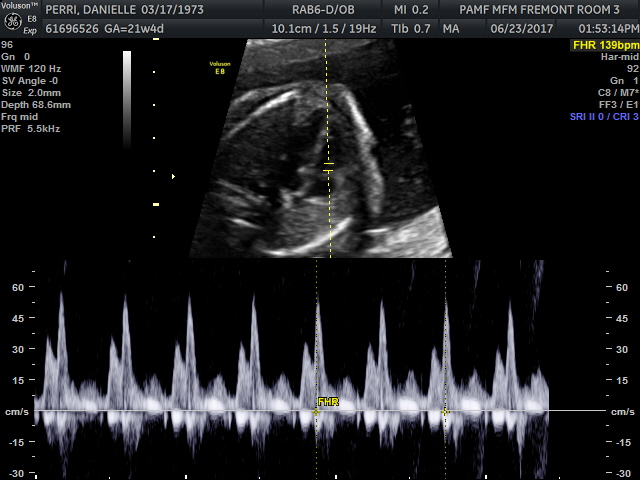

The baby’s heartbeat was 139 beats a minute, a hair slower than 140 last visit and both within the healthy range. I even was given a photo of the heart chamber and the heartbeat pattern on the commemorative CD they gave afterwards.